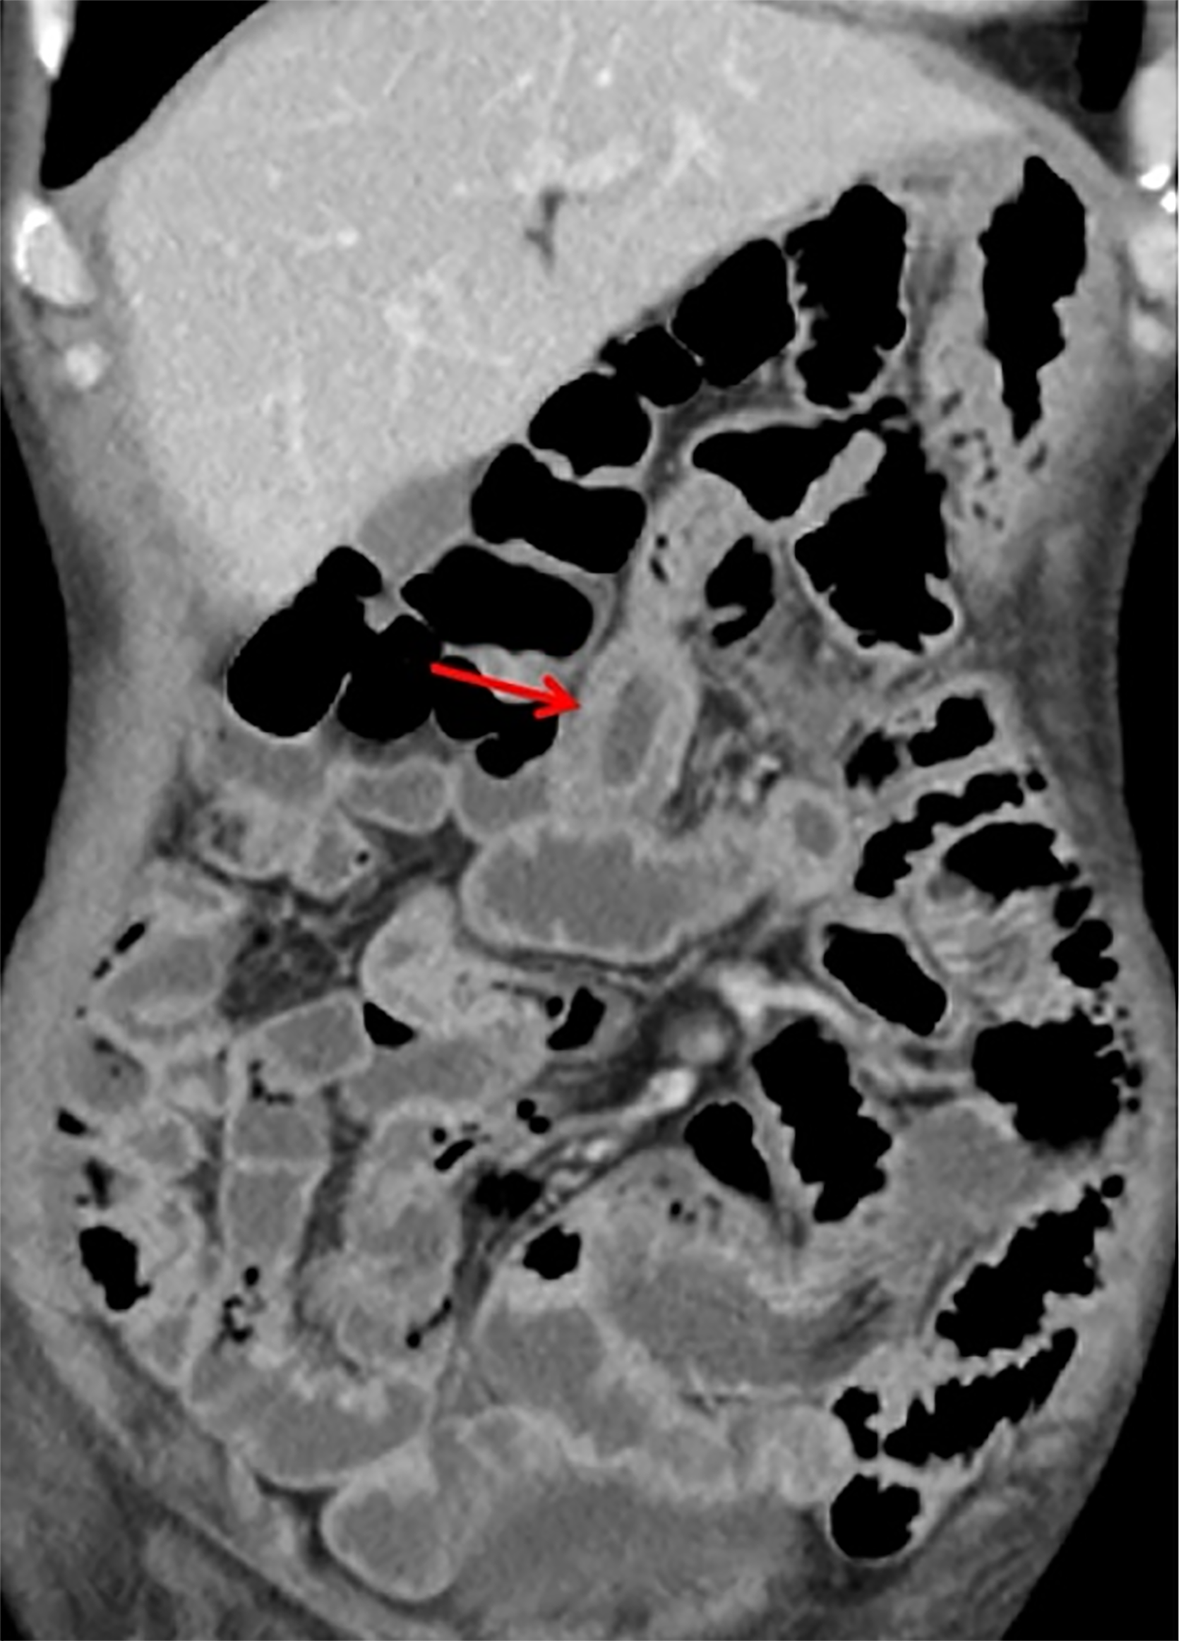

Computed tomography of the small intestine revealed diffuse thickening of the intestinal wall in the distal small intestine (jejunum) at the anastomosis site, with flattening of the intestinal folds (Figure 1). Subsequently, we performed 99Tcm-human serum albumin scintigraphy for intestinal protein loss, as follows: In the blood flow phase, imaging was initiated immediately following intravenous administration of the tracer, with no abnormal focal uptake detected in the abdominal cavity. In the delayed phase, serial imaging was conducted at 2, 5, 10, 15, 20, 25, and 30 minutes and 1, 2, 4, and 5 hours post-injection, to dynamically assess the distribution of abdominal radioactivity. The colon could not be distinctly visualized at any point during the imaging process. Gastroscopy showed good healing at the anastomosis site, with mucosal swelling 10-15 cm proximal to the output loop, with changes suggestive of lymphatic vessel dilation. Rapid urease testing for Helicobacter pylori was negative. Histopathological examination of a small intestine mucosal biopsy from the output loop revealed marked hyperplasia of the lymphoid tissue in the lamina propria, with nondestructive lymphocytic infiltration diffusely distributed between glandular structures without inducing damage. The infiltrating cells were small to medium in size, with mildly irregular nuclei, and some exhibited abundant pale-stained cytoplasm (Figure 2). Immunohistochemical analysis revealed CD3(++), CD7(++), CD56(++), CD20 (partially weak+), CD21 (FDC+), CD2 (partially+), CD4 (scattered+), CD5(-), CD8 (scattered+), Bcl-6(-), CD23 (FDC+), Cyclin D1(-), and a Ki-67 index of 70%. In situ hybridization revealed EBER(-), confirming that the proliferating lymphocytes were of NK-cell origin and consistent with an iNKLPD (Figure 3).